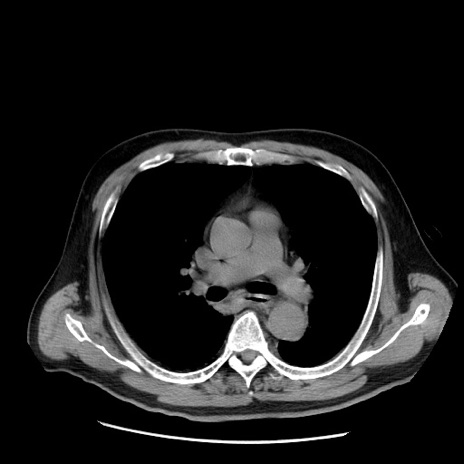

症例20(横断像)

【症例】 60歳代男性

【主訴】 腹部膨満、嘔吐

【現病歴】5日前頃より倦怠感を認め食事量減少し4日前の朝嘔吐、食事摂取困難となった。 3日前近医受診し点滴施行され整腸剤などを処方された。 当日他院を受診し、腹部膨満著明、炎症反応の上昇(CRP10.8、WBC11200)あり、紹介受診となる。

【身体所見】 意識JCS1 受け答えがはっきりしないBP 111/57mHg、 P 67bpm、、BT35.2°C、SpO2 97%(RA)、 腹部:膨隆、打診で鼓音あり、全体的に圧痛有り、腸蠕動音(-)、反跳痛ははっきりせず。

【データ】WBC 11400、CRP 14.20